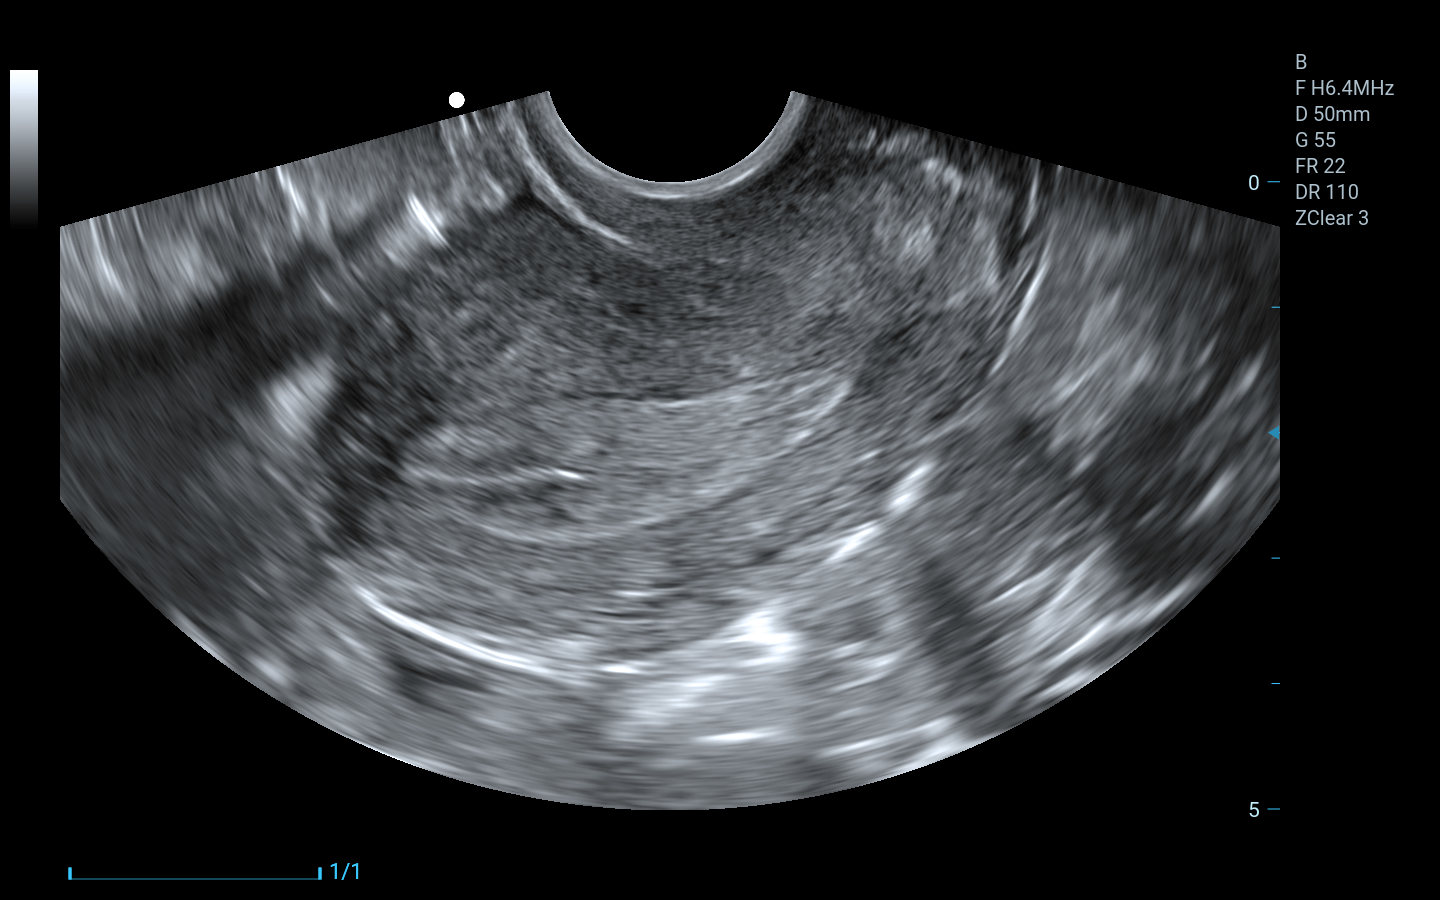

Abdomen, Obstetricia y Ginecología

Piso pélvico

Endocavitario (transvaginal)

Imágenes clínicas extraordinarias